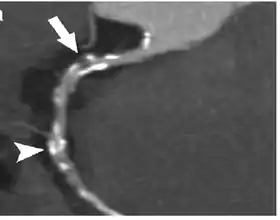

![]() Image of contrast enhanced dual-source coronary CT-angiograph | |

Coronary CT angiography (CTA or CCTA) is the use of computed tomography (CT) angiography to assess the coronary arteries of the heart. The patient receives an intravenous injection of radiocontrast and then the heart is scanned using a high speed CT scanner, allowing physicians to assess the extent of occlusion in the coronary arteries, usually in order to diagnose coronary artery disease.